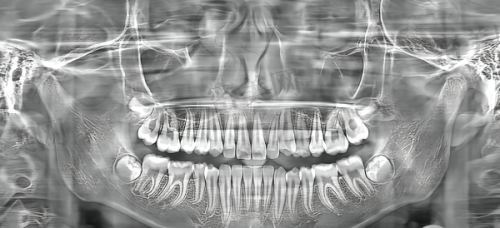

牙博士太仓院区设置了多个科室,包括牙齿洁治、补牙、拔牙、根管治疗、牙齿矫正、儿童牙科、种植牙、牙周病治疗、口腔修复、全口义齿等,几乎涵盖了口腔诊疗的所有常见项目,真正实现“拎包来、带笑走”。特别是种植牙和隐形矫正,是这里的热门项目,接受度非常高。针对怕疼的患者,这里还引入了舒适化口腔诊疗设备,比如微痛麻醉、数字化根管治疗仪、口腔摄影系统等,让看牙这些“怕痛党”少了特别多恐惧感。